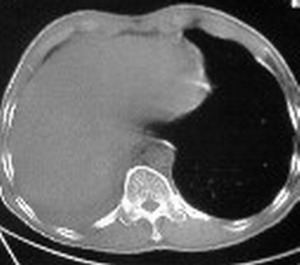

1:右侧结核性胸膜炎,胸腔积液;

2:不排除右肺癌。

影像特征很象,包裹性胸腔积液,建议楼主测ct值鉴别.

考虑中心型肺癌伴下叶不张,肺底积液吧。

右肺下野后部均匀低密度影,边缘锐利,前缘外突(不支持肺不张),纵隔内未见明显肿大淋巴结,右下肺门结构显示欠清,临床资料太过简单,考虑右侧后胸部包裹性积液。其他待排。建议密切结合临床其他检查。

考虑右下肺中心型肺癌伴下叶肺不张、胸腔积液。

ct值12,包裹性胸腔积液,